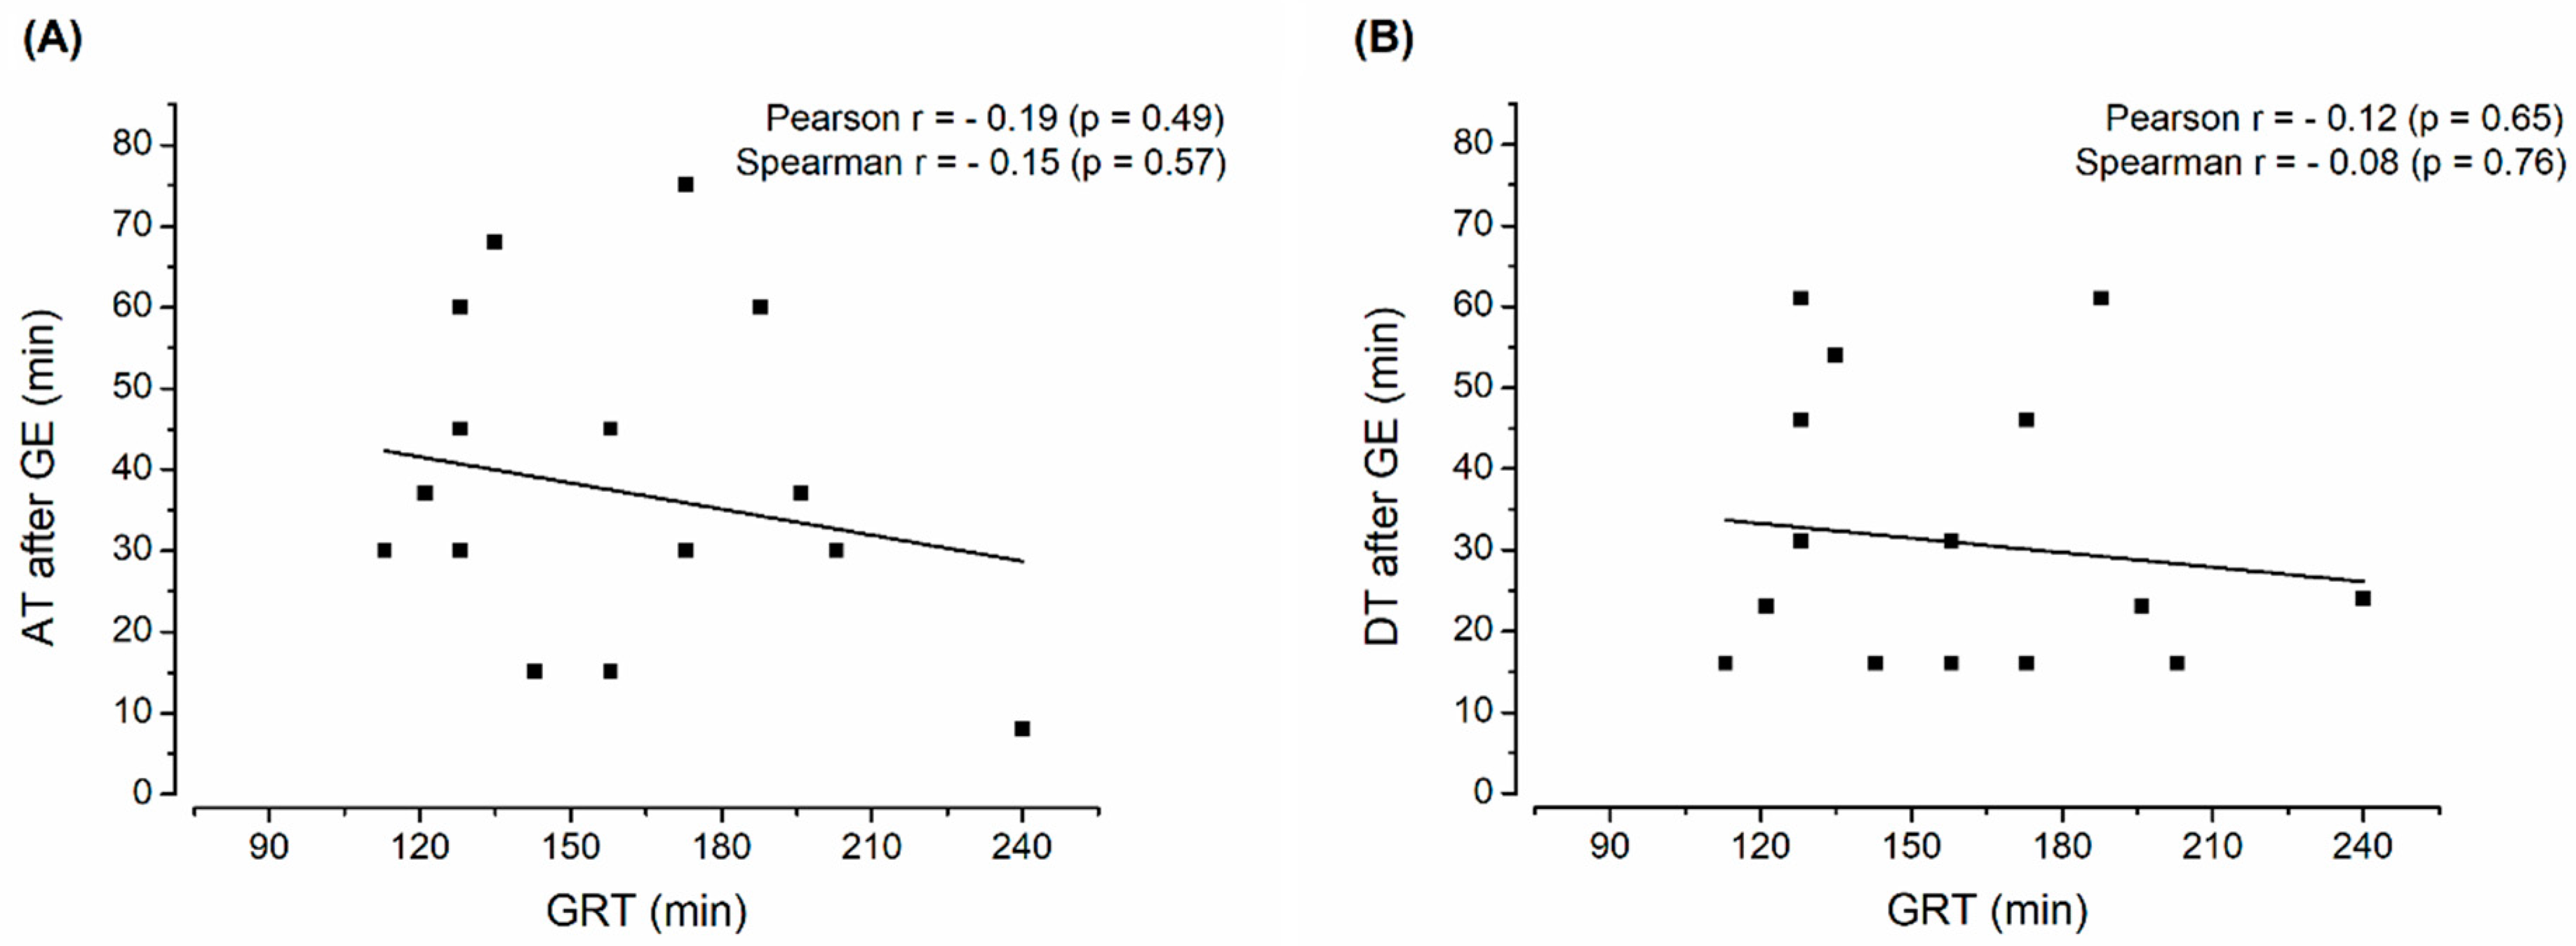

3. Results and Discussion